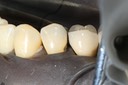

Kyle Chock #2 finish